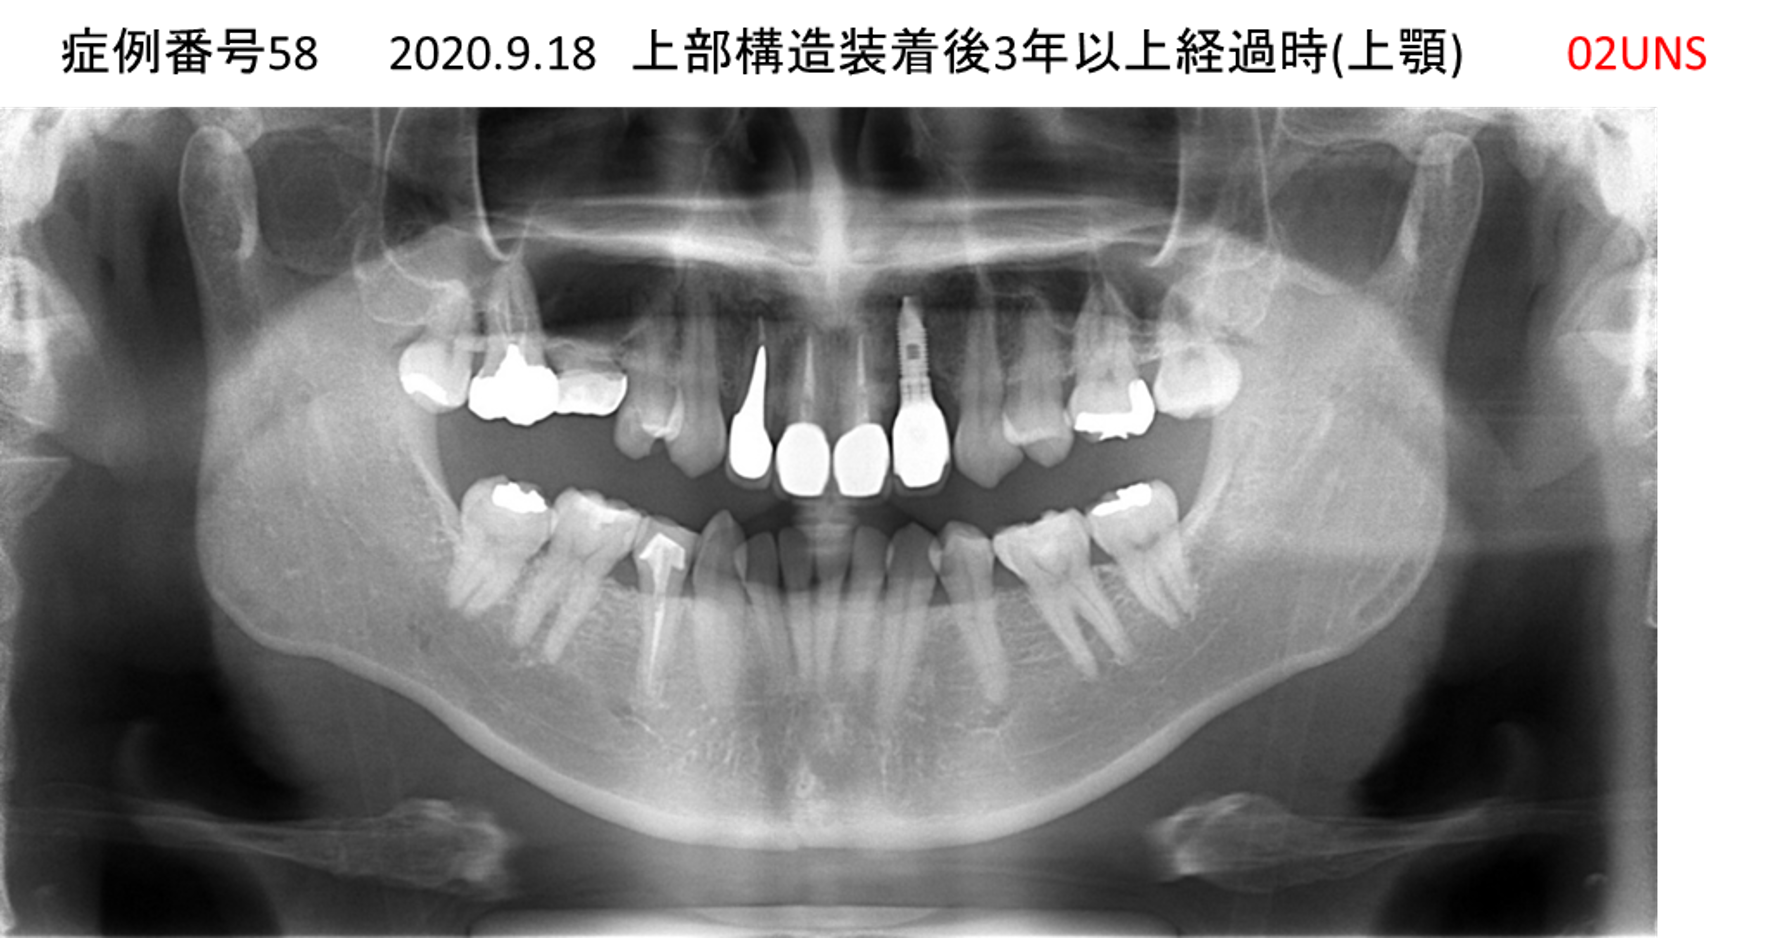

食事ができない/噛めない患者様のインプラント症例

| 治療名称 |

インプラント |

| 治療費用 |

540万円+税 |

| 治療期間 |

6か月 |

| 患者さんの症状(主訴) |

食事ができない。噛めない。上の前歯が揺れてきた。入れ歯がつらい。 |

| 治療内容 |

サイナスリフト、インプラント |

| 治療結果 |

なんでも食べられるようになった。力が入る(全身)ようになった。 |

| 治療の注意点(リスク/副作用) |

インプラントが壊れたら再治療が必要 |